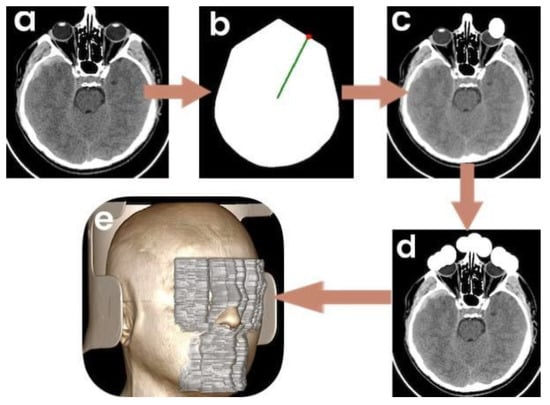

- −

- A presence of image artifacts that could potentially complicate the AI service operation (dynamic artifacts, bone and/or metal artifacts, artifacts from detector malfunction);